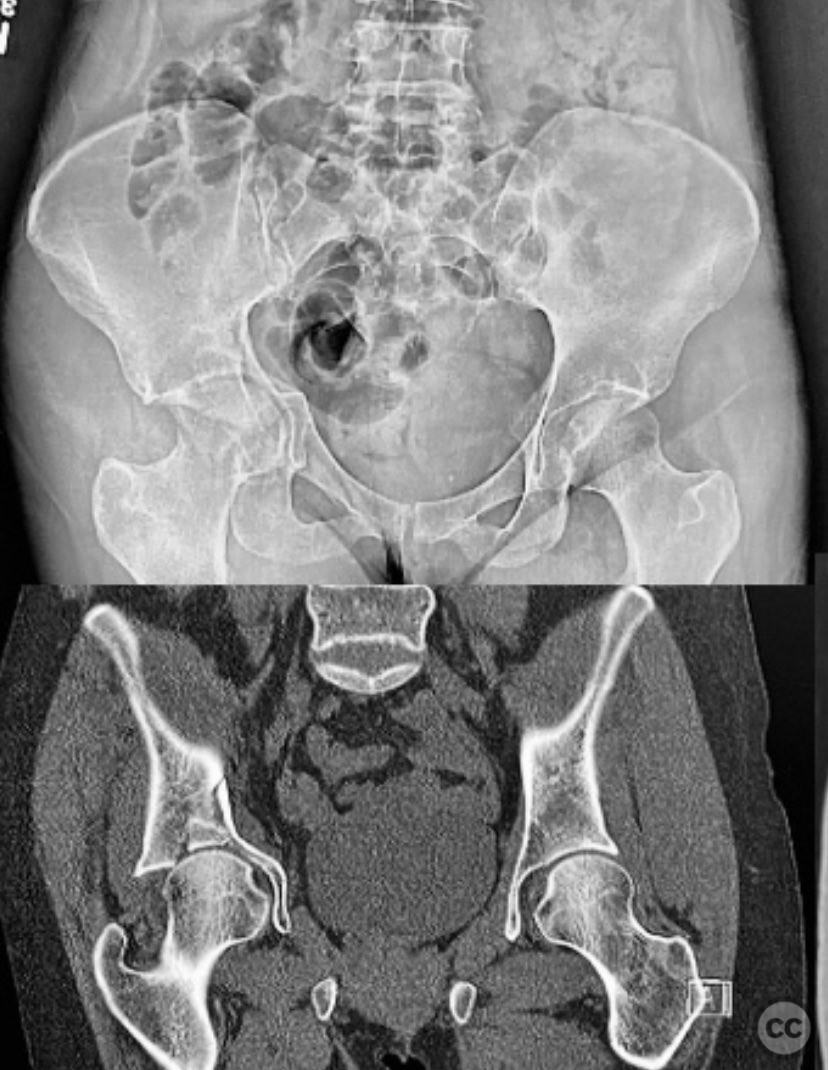

Clinical and radiological findings:  An active senior patient sustained an intruded acetabular fracture, best classified as an anterior column/posterior hemi-transverse (AC/PHTr) pattern with associated medial dome impaction. Initial evaluation included clinical and radiological assessment, with CT imaging confirming the fracture configuration and impaction zone. Neurovascular examination was not specified. Skeletal traction of 10-15 pounds was applied during initial resuscitation and evaluation.

Postoperative protocol:   Postoperatively, weight bearing was protected for 4-6 weeks using crutches or a walker as tolerated, though most patients weight bear as tolerated for various reasons.